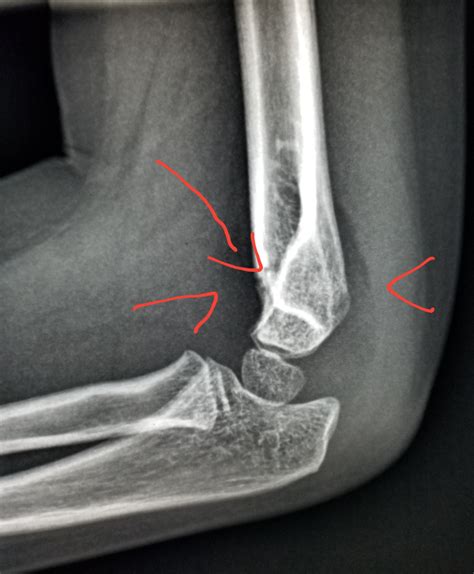

• Imaging Tests: X-rays are the baseline, but an ultrasound or MRI is far more effective at detecting a small joint effusion because these methods can visualize soft tissues and identify fluid pockets that X-rays might miss.

• small joint effusion elbow